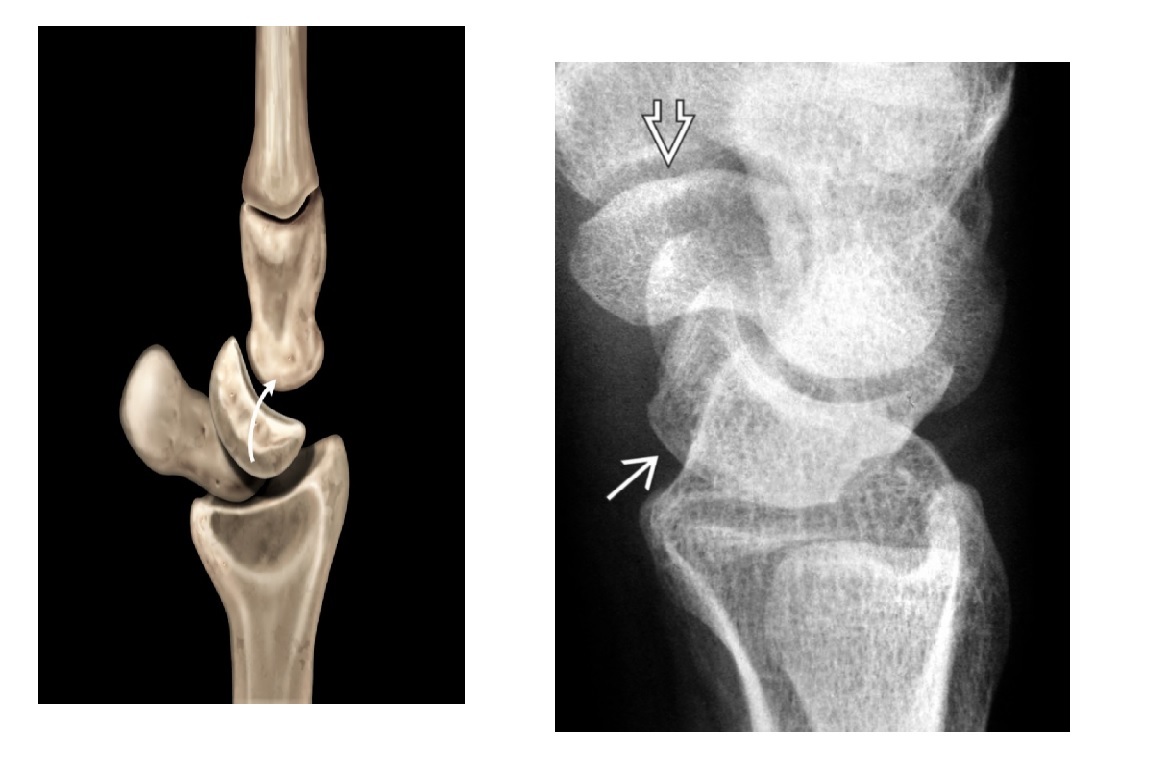

Segond fracture?

A

Lateral tibial plateau

Associated with ACL tear (75%) and internal rotation

MR SL = Medial Reverse Lateral Segond

Reverse Segond fracture?

Medial tibial plateau

Associated with PCL tear with external rotation. Associated with medial meniscus injury.

Arcuate sign ?

Avulsion of the proximal fibula

Associated with PCL tear